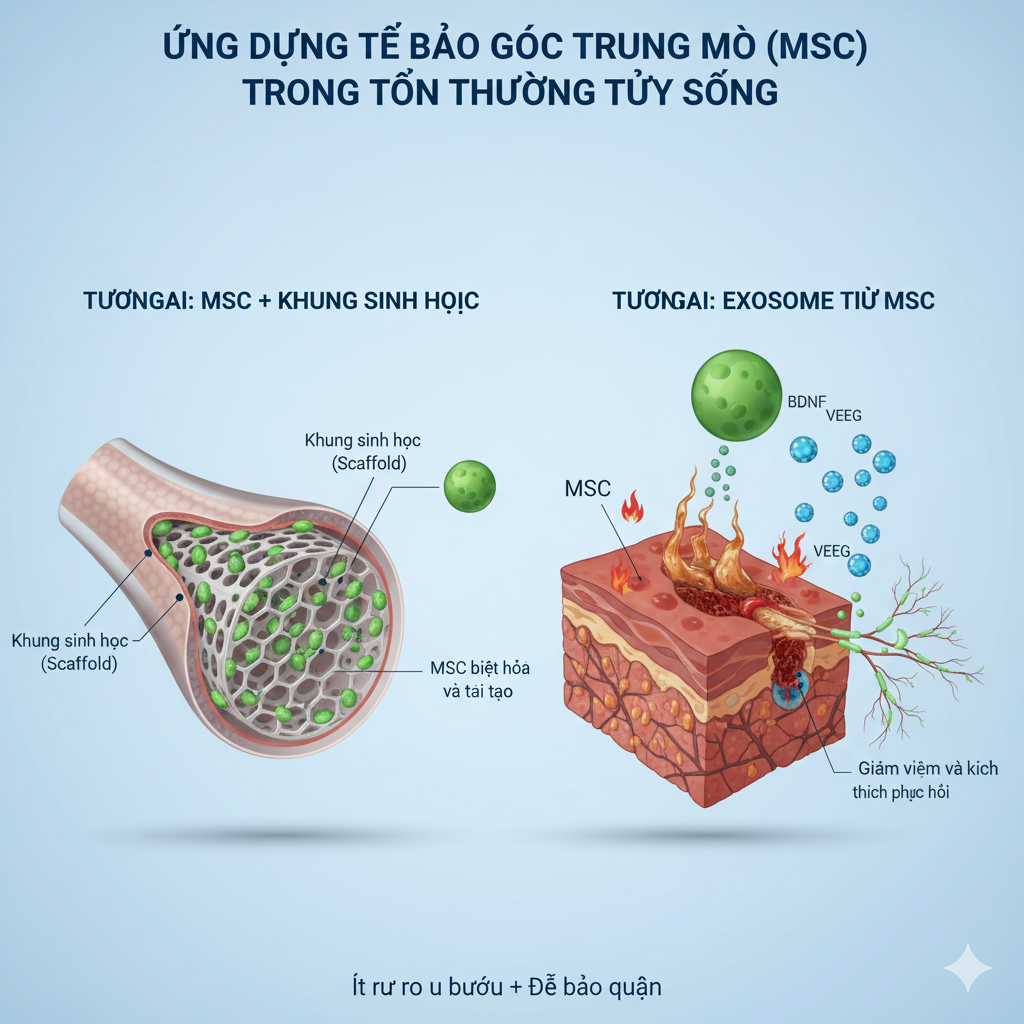

Các phác đồ được xây dựng dựa trên báo cáo khoa học

Đội ngũ có kinh nghiệm trong tế bào gốc, miễn dịch học, công nghệ sinh học, y học phân tử